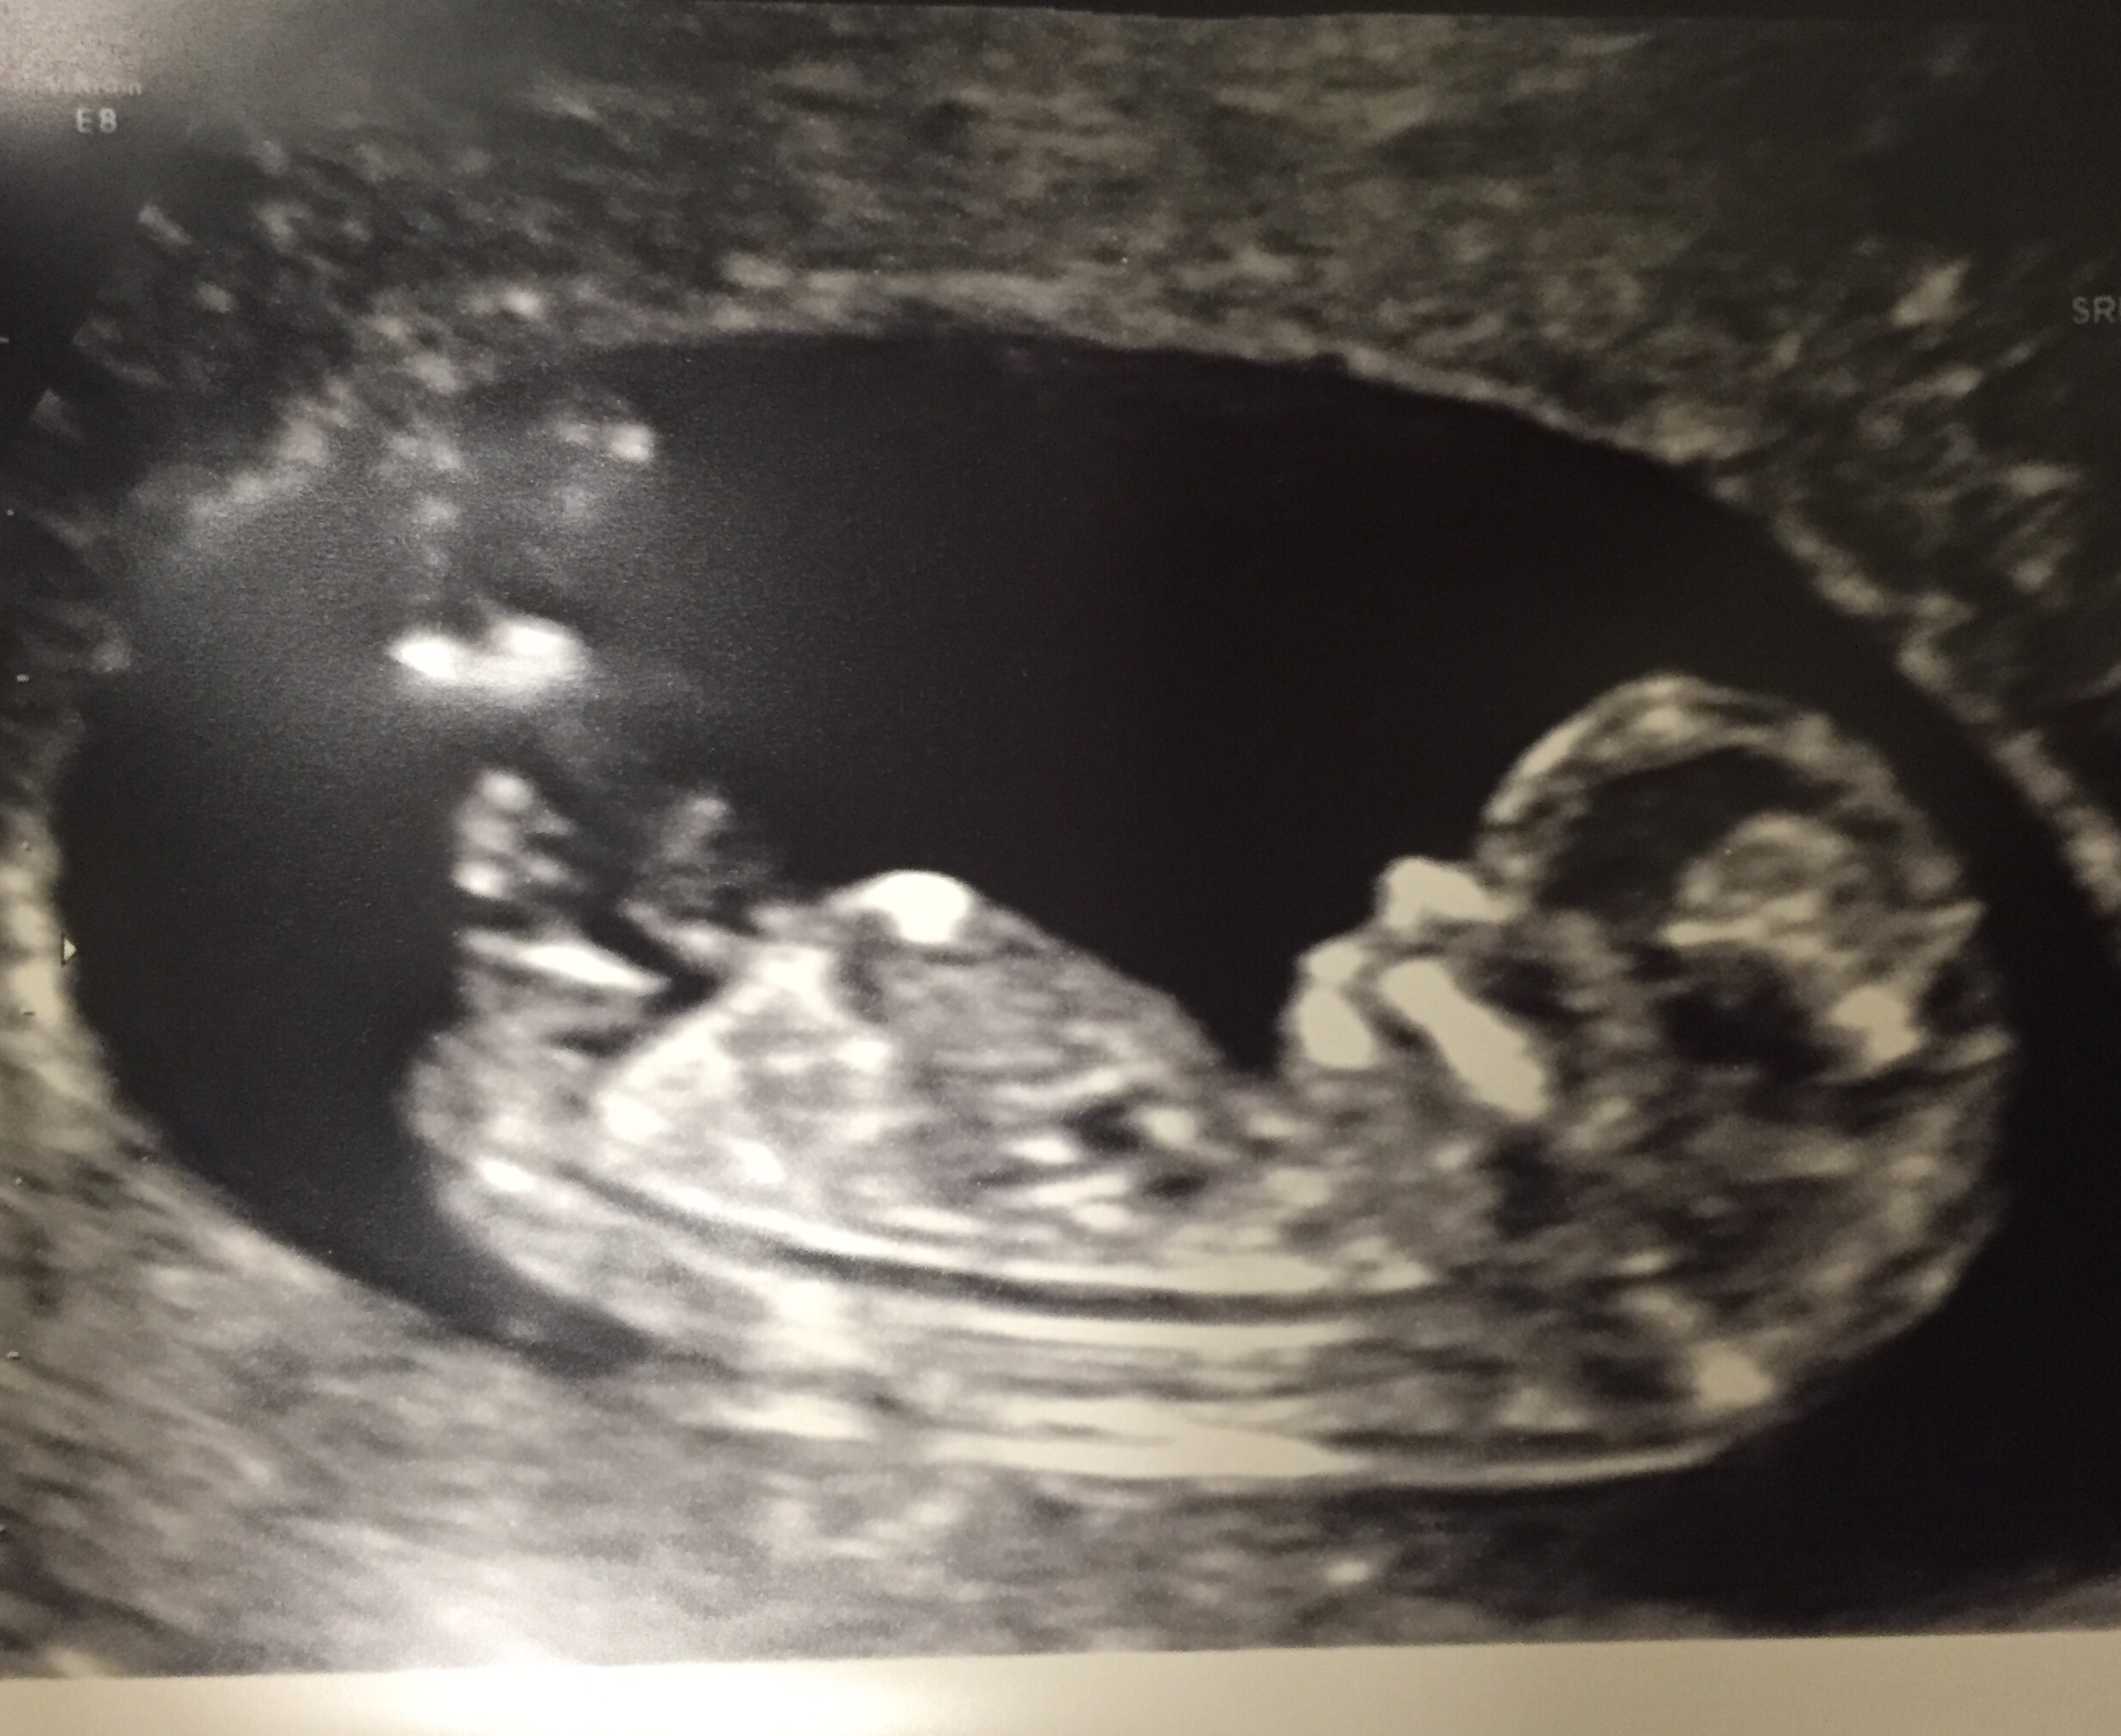

Had my 12 week 2 day sonogram yesterday! Baby is healthy and was moving all over the place, but since he/she was literally doing a headstand they had a hard time getting the measurement, so I have to get another one next week!